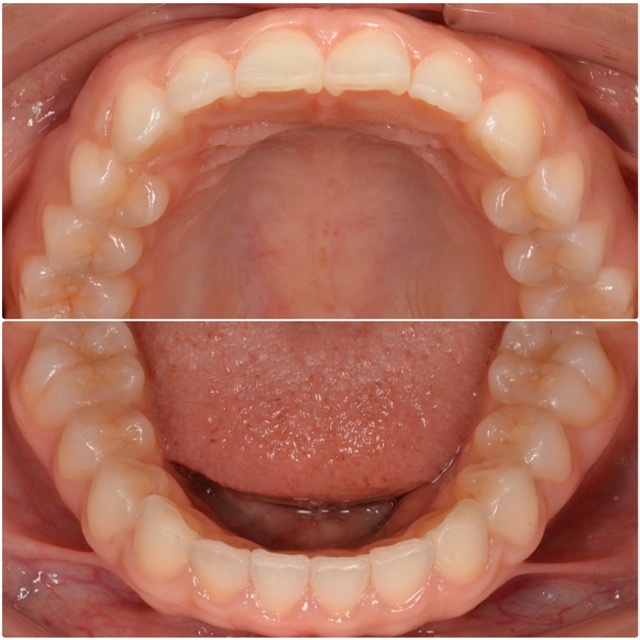

写真の症例は費用を抑えて歯並びを治したいとの事でご来院頂きました。

特に上の前歯に、ねじれ(捻転)がありました。この状態は見た目を損なうだけでなく加齢と共に偏摩耗の原因となります。下顎と合わせて改善していきました。また、費用を抑えたいとの事でしたので前歯部のみのマウスピース矯正を行いました。とても歯並びが綺麗になり、治療期間も半年で終了したのでもっと早く治療費しておけば良かったというお声を頂きました!